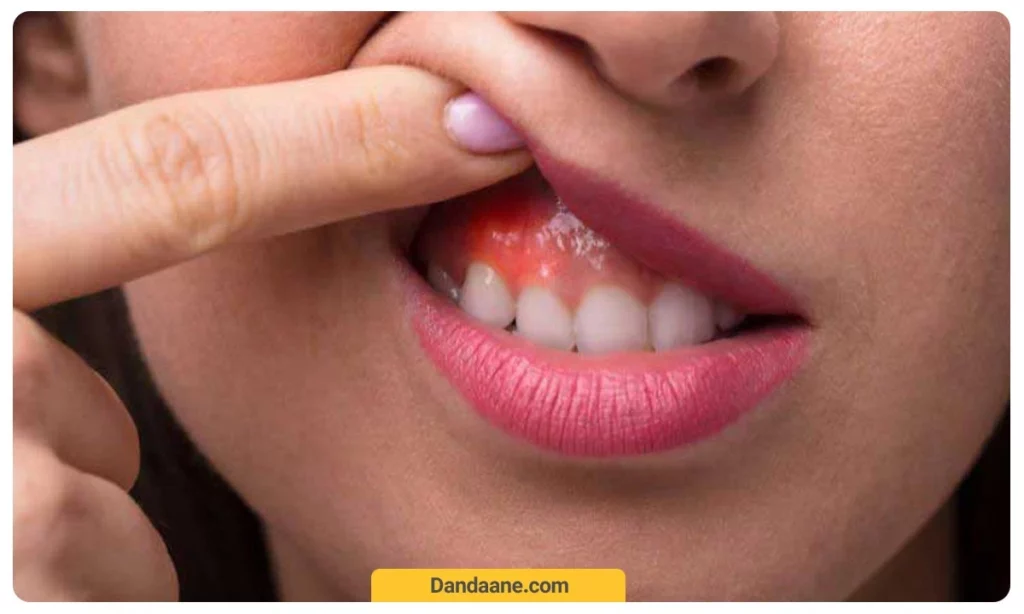

- عفونت و التهاب لثه: ورود باکتری ها به ترک های دندان می تواند منجر به عفونت شود.

بله، اگر ترک دندان عمیق باشد و باکتری ها وارد آن شوند، ممکن است باعث عفونت لثه یا پالپ دندان شود. در این موارد، عصب کشی دندان ممکن است ضروری باشد تا از گسترش عفونت جلوگیری شود.